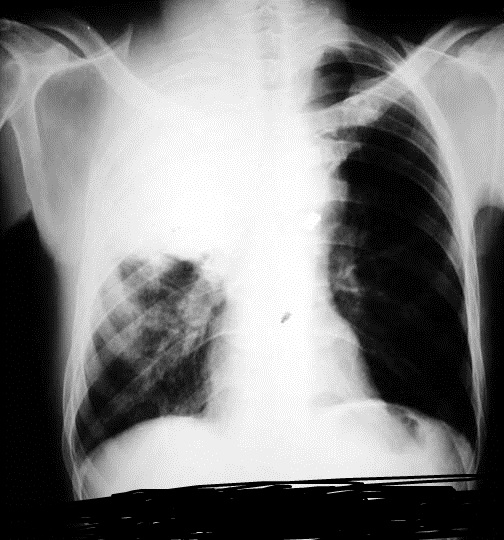

340) A 52 year old woman with history of triple-negative, metastatic breast cancer presents to the Emergency Room with increasing shortness of breath. This is her third Emergency room visit in the past 2 months. Earlier, she was admitted to the hospital twice for massive pleural effusion and underwent therapeutic thoracentesis. She was told that the cancer had spread to her lungs and pleura. She received multiple courses of chemotherapy in the past and her cancer has progressed despite initial response to chemotherapy. Her oncologist recommended palliative care. On examination, she is afebrile, respiratory rate is 24/min, Blood pressure 120/70 mm Hg and Heart Rate 106/min. Breath sounds are decreased on right side of the chest. D-dimer level is 60ng/ml ( normal < 500 ng/ml) . A chest X-ray is shown below:

Which of the following management options is most appropriate for this patient?

A) Obtain Pleural biopsy

B) Tube thoracostomy and Pleurodesis

C) Start Heparin and obtain CT Angiogram

D) Pleuro-perintoneal shunt

E) Repeat Therapeutic thoracentesis

Filed under: Uncategorized, USMLE Test Prep | Tagged: Archer cardiology, Archer oncology, archer palliative care, Archer pulmonology, Archer radiology, USMLE STEP 3 CARDIOLOGY, USMLE STEP 3 ONCOLOGY, usmle step 3 palliative care, USMLE STEP 3 PULMONOLOGY, USMLE STEP 3 RADIOLOGY | 17 Comments »